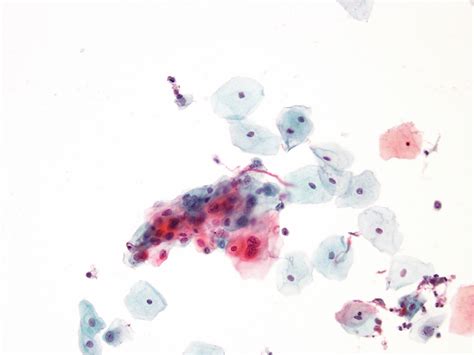

Célulasescamosasatípicasdesignificadoindeterminado(ASC-US).ASC-UScan be controlled by HPV triage because most reactive changes will be negative. Monitoring HSIL, LSIL andASCrates forms a useful method of quality assurance.

Célulasescamosasatípicasdesignificadoindeterminado(ASC-US).Célulasescamosasatípicasdesignificadoindeterminadoo incierto. 10-20%, base LIP de alto grado. Resultado preliminara, cambios no cancerosos, inflamacion en la cervix.